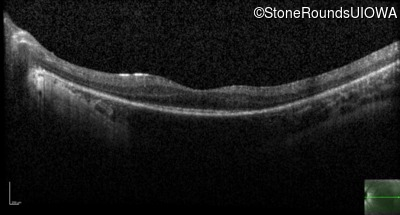

Optical Coherence Tomography - Left - 20/70

Exemplar / OCT Stack